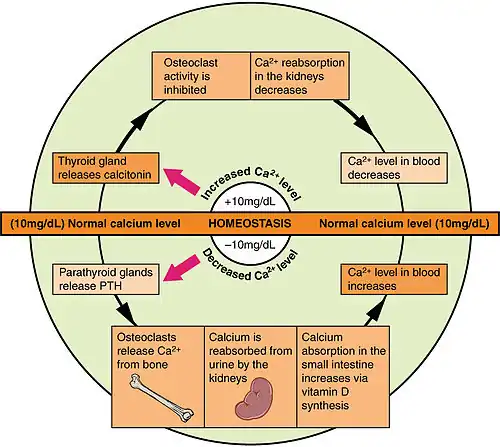

- Vitamin D deficiency:[42][43] Low circulating Vitamin D is common among the elderly worldwide.[4] Mild vitamin D insufficiency is associated with increased parathyroid hormone (PTH) production.[4] PTH increases bone resorption, leading to bone loss. A positive association exists between serum 1,25-dihydroxycholecalciferol levels and bone mineral density, while PTH is negatively associated with bone mineral density.[4]

The three main mechanisms by which osteoporosis develops are an inadequate peak bone mass (the skeleton develops insufficient mass and strength during growth), excessive bone resorption, and inadequate formation of new bone during remodeling, likely due to mesenchymal stem cells biasing away from the osteoblast and toward the marrow adipocyte lineage.[107] An interplay of these three mechanisms underlies the development of fragile bone tissue.[37] Hormonal factors strongly determine the rate of bone resorption; lack of estrogen (e.g., as a result of menopause) increases bone resorption, as well as decreases the deposition of new bone that normally takes place in weight-bearing bones. The amount of estrogen needed to suppress this process is lower than that normally needed to stimulate the uterus and breast gland. The α-form of the estrogen receptor appears to be the most important in regulating bone turnover.[37] In addition to estrogen, calcium metabolism plays a significant role in bone turnover, and deficiency of calcium and vitamin D leads to impaired bone deposition; in addition, the parathyroid glands react to low calcium levels by secreting parathyroid hormone (parathormone, PTH), which increases bone resorption to ensure sufficient calcium in the blood. The role of calcitonin, a hormone generated by the thyroid that increases bone deposition, is less clear and probably not as significant as that of PTH.[37]